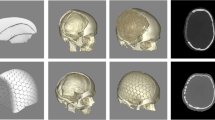

A computer-aided design of a patient-specific porous polyethylene implant was created based on detailed 2 mm bone CT scans. Most designs were based on the shape and curvature of the contralateral side when available. In bifrontal cases, the design engineer collaborated with the neurosurgeon to determine a shape that would work with the patient's anatomy and meet the neurosurgeon's requirements. Bifrontal cases were usually designed in two pieces to facilitate placement (Fig. 1).

The operation was standardized. The entire head of the patient was preoperatively shaved and bandaged with a disinfectant (peroxyacetic acid) for 12 h. Standard intraoperative antibiotic prophylaxis was administered (Cefazolin). During operations, the patient's head was fixed in a Mayfield fixator. After the scalp incision, the skin flap was separated from the dura mater, duraplasty and bony margins. To prevent epidural hematoma, tack-up sutures were routinely used around the edge of the craniotomy. A custom-made PE implant without flange was then inserted into the bone defect. The implant was fixed with miniplates. In cases of bone flap resorption, the partially resorpted bone flap was removed before insertion of the PE implant. The temporalis muscle was separated from the duraplasty and placed above the implant in an orthotopic position (Fig. 2). A vacuum drain was inserted subgaleally for 24 h. Due to the implant's porous structure providing adequate drainage of the epidural space, additional burholes were not performed in the implant. The galea and skin were sutured.